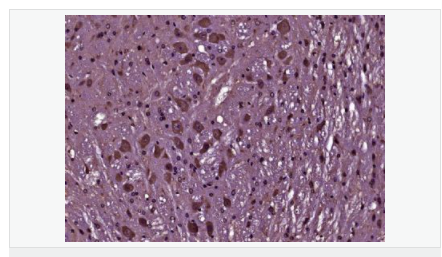

Rabbit anti-Phospho-Bcl-2 (Thr129) Polyclonal antibody

交叉反應(yīng):Human,Mouse,Rat(predicted:Dog,Pig,Cow,Horse,Sheep) 推薦應(yīng)用:WB,IHC-P,IHC-F,IF,Flow-Cyt,ELISA

產(chǎn)品應(yīng)用WB=1:500-2000 ELISA=1:5000-10000 IHC-P=1:100-500 IHC-F=1:100-500 Flow-Cyt=1μg/Test IF=1:100-500 (石蠟切片需做抗原修復(fù))